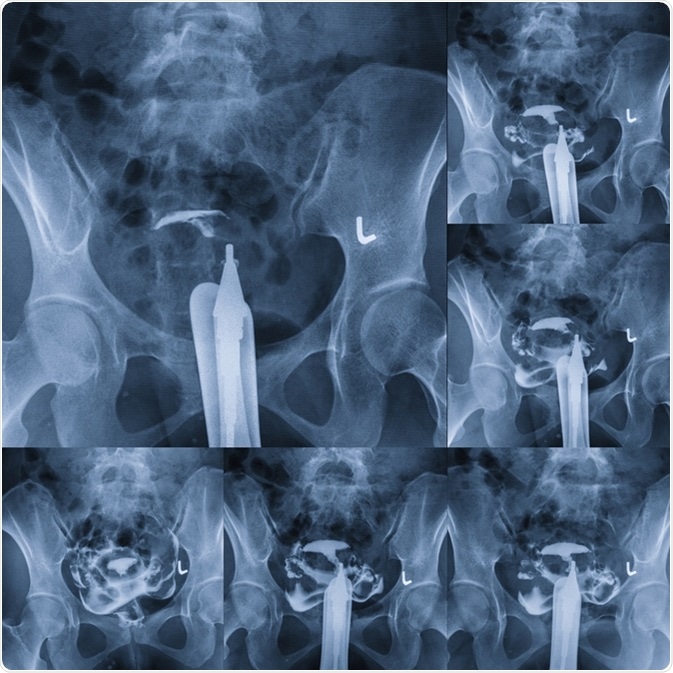

Hysterosalpingography - type of X-ray called fluoroscopy that looks at a woman's uterus and fallopian tubes. Image Credit: MossStudio / Shutterstock

An initial fluoroscopic image is taken to visualize the pelvis, after which the contrast is injected. Subsequently four images are taken at timed intervals to demonstrate the dye outlining the interior of the uterus, the filling of the fallopian tubes, and the potential spilling of the dye into the peritoneal cavity through the open or fimbrial end of each tube. This spill-over confirms tubal patency.

In some cases, no spillage is seen on one or both sides because of tubal spasm rather than blockage. To rule this out, in such cases an antispasmodic agent such as scopolamine is administered intravenously, followed by the injection of more contrast. More images are taken once the patient’s heart rate increases (which is another effect of this drug), showing that it is taking effect. The accumulated images record the early filling of the uterus, complete filling of the uterus, tubal filling, and spillage of the dye.